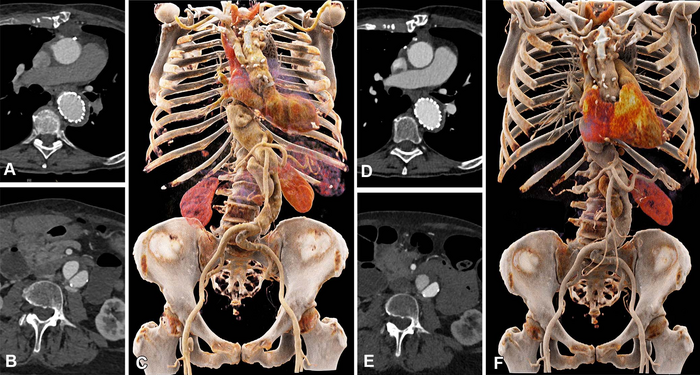

OAK BROOK, Ill. (January 26, 2023) – Photon-counting detector CT reduces the amount of contrast needed for CT angiography (CTA) while maintaining image quality, according to a new study published in Radiology: Cardiothoracic Imaging , a journal of the Radiological Society of North America ( RSNA ).

Photon-counting detector CT is a new technology that can acquire high-quality images at lower contrast media volume than conventional CT scanners that rely on energy-integrating detectors. It also offers diagnostic quality images at lower radiation dose than those of conventional CT.

Dr. Alkadhi and his University Hospital colleague Kai Higashigaito, M.D., led a study that looked at a low-volume contrast media protocol with photon-counting detector CT for CTA of the aorta in the chest and abdomen.

The study included 100 people, mean age 75. Patients underwent CTA with photon-counting detector CT of the aorta in the chest and abdomen. The patients had received a previous CTA with conventional CT at equal radiation doses.

Photon-counting CT had a higher contrast-to-noise ratio, a key measure of image quality, which translates to a low-volume contrast media protocol. Contrast media volume was reduced by 25%.

Two independent readers rated the image quality of photon-counting CT as higher than that of conventional CT at an equal radiation dose.

“We showed that the improved image quality of CTA with photon-counting detector CT systems can be used to reduce the amount of administered contrast media to the patients, without reducing the diagnostic yield of the examination,” Dr. Alkadhi said. “Image quality remained at the same level as that of previous CT angiography examinations in the same patients using a conventional CT, despite the fact that we reduced the contrast media volume.”